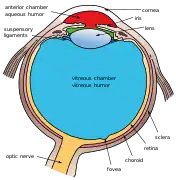

Anatomy of the anterior part of the human eye. "Suspensory ligaments" are labeled at left. | |

The zonule of Zinn (/ˈtsɪn/) (Zinn's membrane, ciliary zonule) (after Johann Gottfried Zinn) is a ring of fibrous strands forming a zonule (little band) that connects the ciliary body with the crystalline lens of the eye.[1] These fibers are sometimes collectively referred to as the suspensory ligaments of the lens, as they act like suspensory ligaments.

The zonule of Zinn is split into two layers: a thin layer, which lies near the hyaloid fossa, and a thicker layer, which is a collection of zonular fibers. Together, the fibers are known as the suspensory ligament of the lens.[4] The zonules are about 1–2 μm in diameter.[5]

The zonules attach to the lens capsule 2 mm anterior and 1 mm posterior to the equator, and arise of the ciliary epithelium from the pars plana region as well as from the valleys between the ciliary processes in the pars plicata.[6][7]